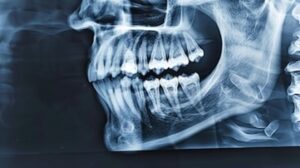

Understanding the Causes of a Fractured Jaw A mandibular fracture can occur for various reasons. Commonly, it happens due to accidents, like car crashes or